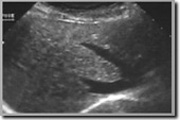

echo lever echotoestel

pre natale echo

Opvolging van de groei van de foetus tijdens de zwangerschap